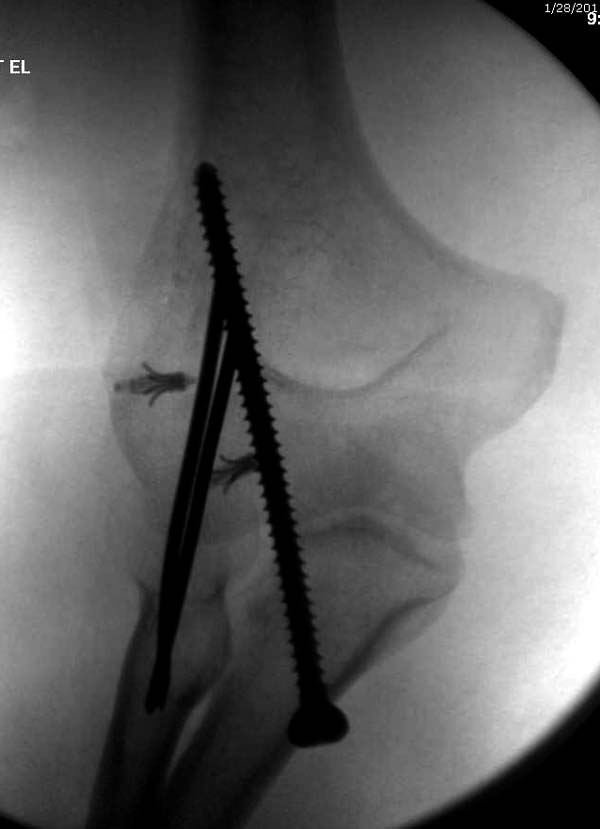

Несмотря на отрицательный отзыв, некоторые нестабильные вывихи лечим

трансартикулярным методом. Тонкие спицы ломаются и имеют риск

внутрисуставной инфекции. Винты 3.5 мм не выдерживают, а более толстые

каннюлированные винты неплохо проявили себя. Неосторожность при

установке приводила к поломке тонких guide wire внутри сустава. Лучшие

кортикальные в 4.5 мм и гипс на три недели. Винт удаляется, затем

разработка сустава.

Снимки: 1-2 вывих, 4-5 вторичное смещение в гипсе, реконструкция

перевод в наш центр; 18-21 временная фиксация, 22-25 трансартикулярная

фиксация и нестабильная головка фиксирована спицами, 29-30 амбулаторно,